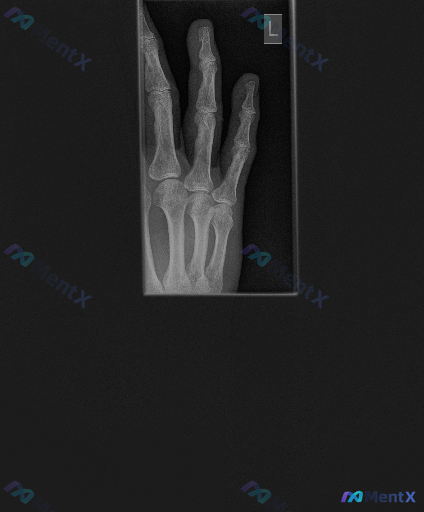

整理了一份左手手指的X光影像资料,大家来一起看看思路会怎么走。 核心影像表现: - 中指及无名指近节指间关节(PIP)间隙狭窄,中指尤为明显 - 部分关节面边缘骨质改变,不够光滑,可见边缘骨赘形成 - 关节面边缘有不规则虫蚀样/缺损样骨质改变,骨密度不均 - 中指PIP关节周围软组织明显梭形肿胀 -...

各位同道,这里有一份左手正位X光片的影像学表现供大家讨论。 影像观察 - 骨性结构:各掌骨及指骨皮质连续性尚可,未见明显新鲜骨折线及移位;腕骨排列大致有序,未见明显舟骨腰部骨折或钩骨骨折征象;整体骨密度未见明显异常,骨小梁结构清晰,未见明显局部溶骨性破坏或成骨性改变;受检者骨骺线均已闭合,提示为成年...

整理了一个病例,45岁男性,6个月疲劳加剧伴性欲减退,双手关节疼痛,有高血压病史,血压控制可,不吸烟,周末仅喝2-3瓶啤酒。体征:皮肤色素深,睾丸缩小,双手第二三掌指关节触痛、活动受限,肝肋下2-3cm可触及。化验:铁蛋白250μg/L,AST70U/L,ALT80U/L,血糖250mg/dL。 问...